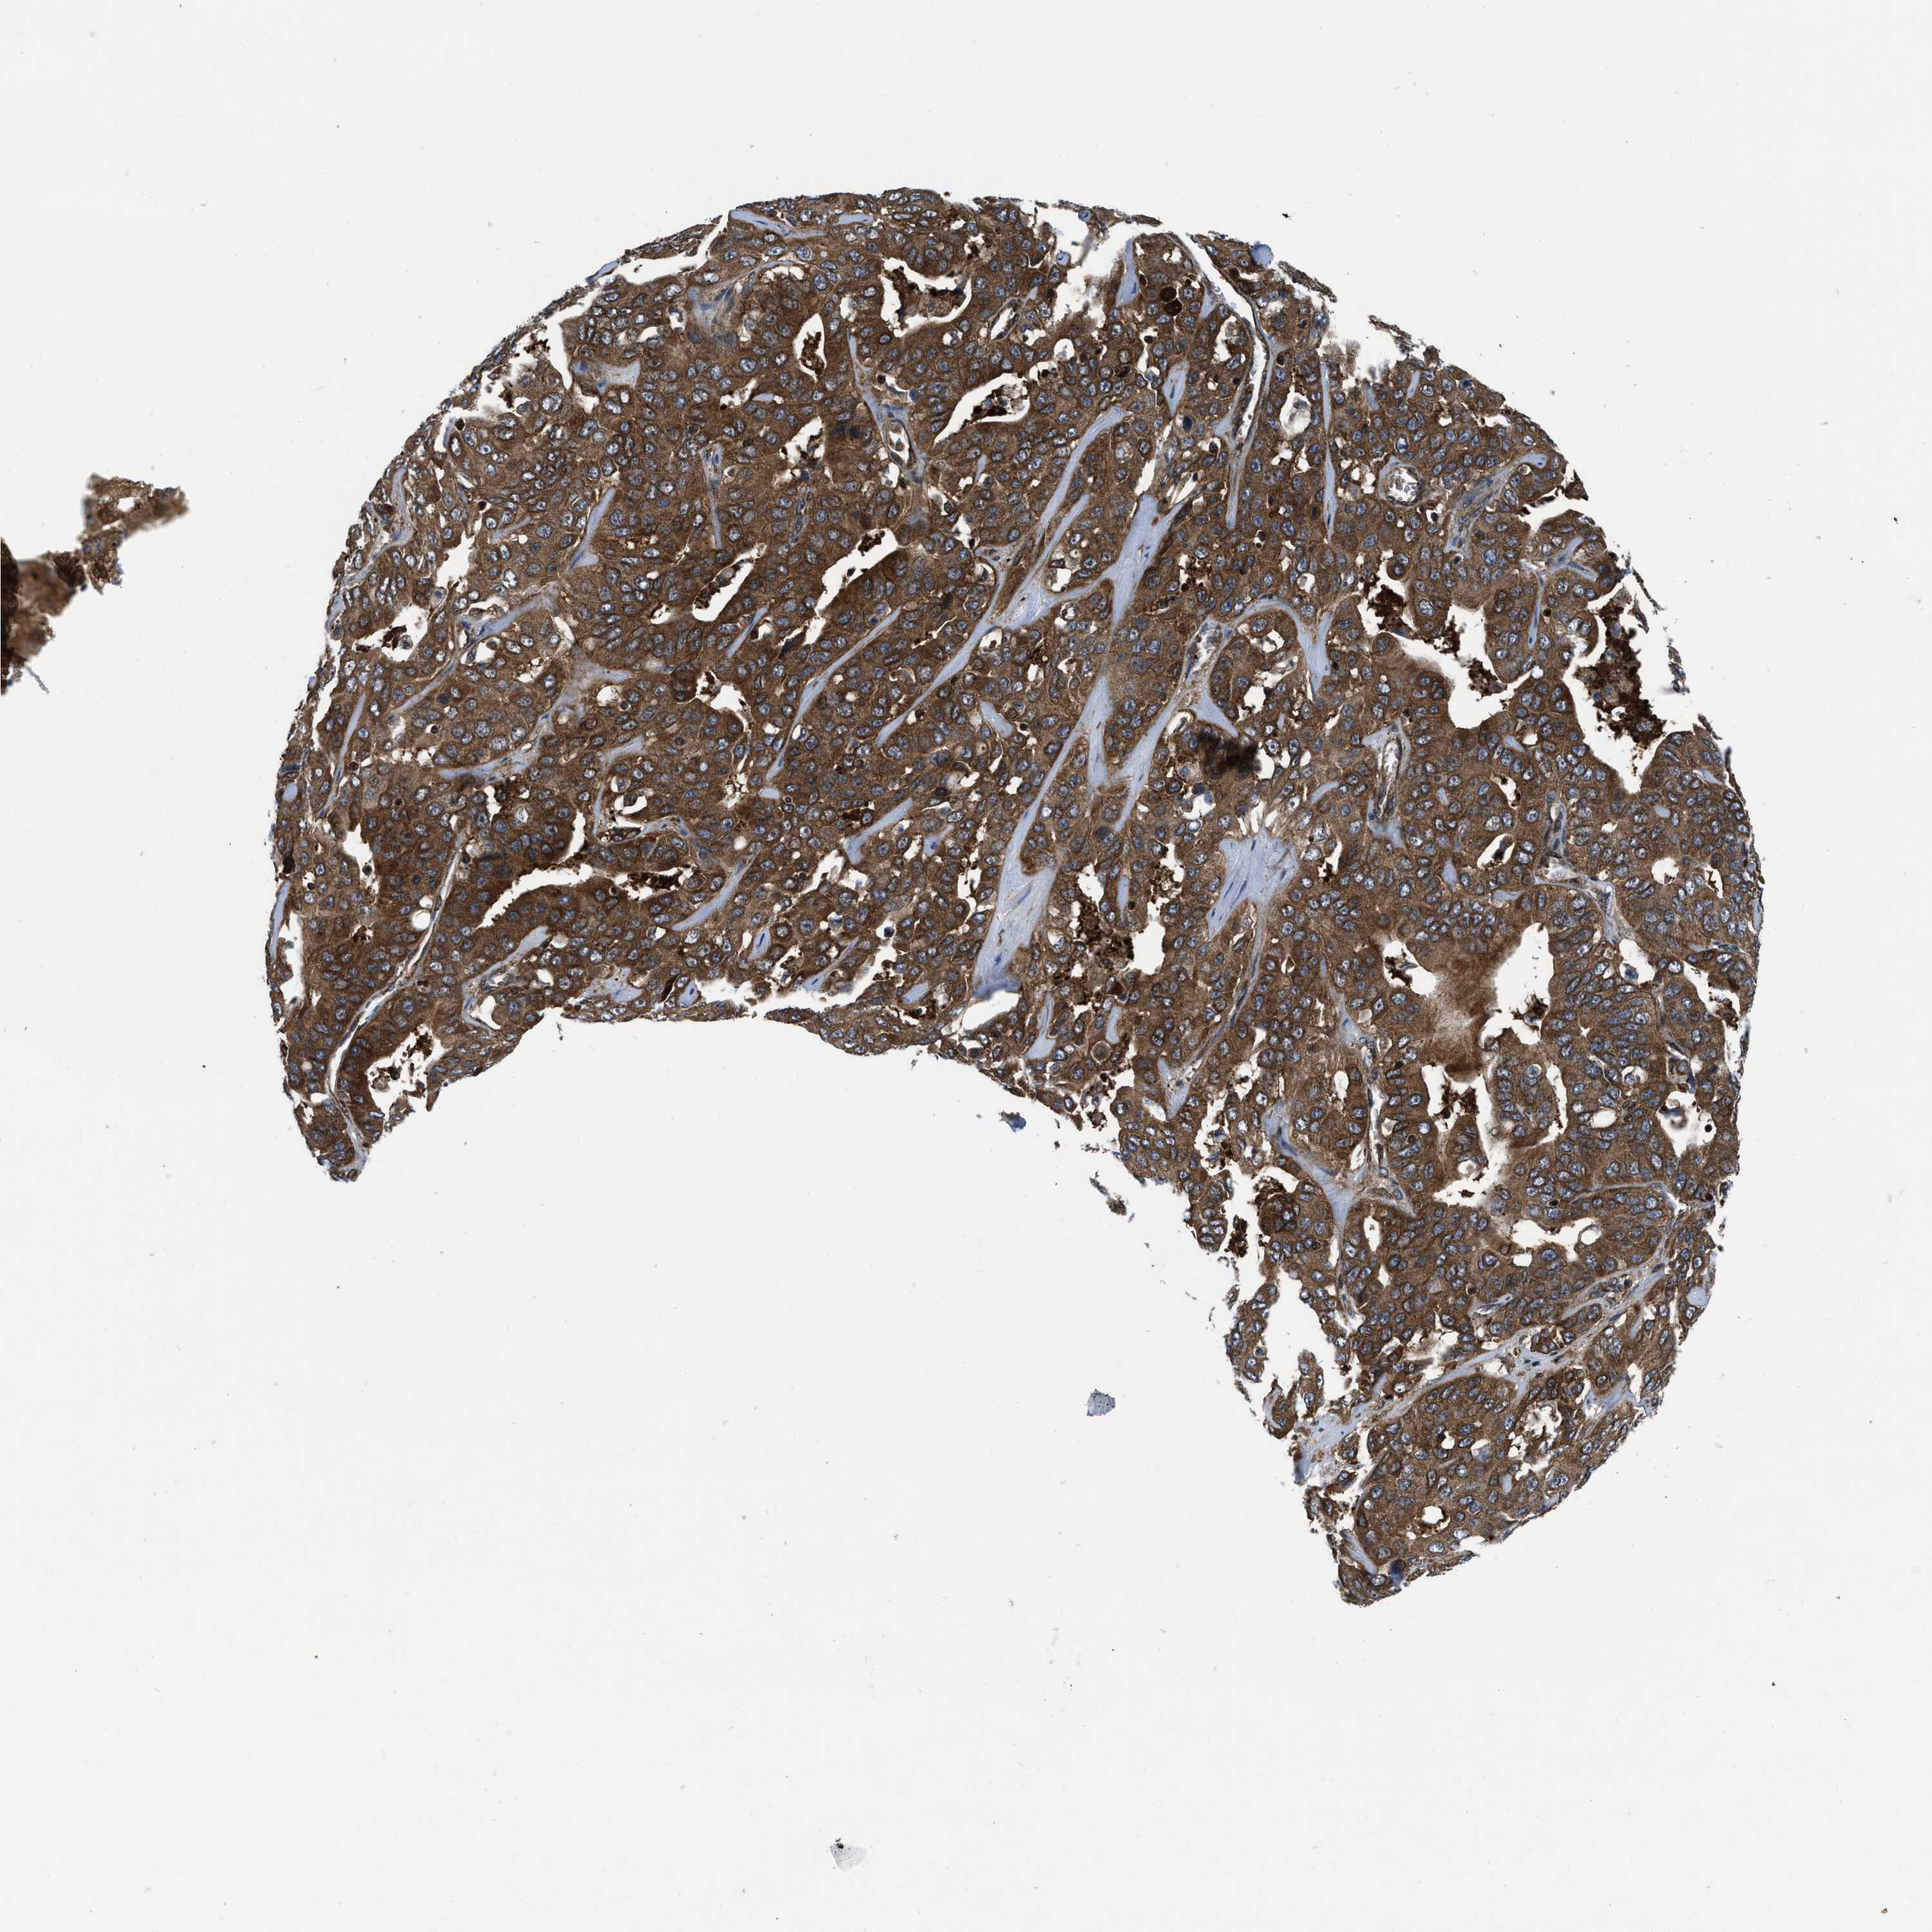

LIVER CANCER - Protein expressioni

A mouse-over function shows sample information and annotation data. Click on an image to view it in a full screen mode. Samples can be filtered based on level of antibody staining by selecting one or several of the following categories: high, medium, low and not detected. The assay and annotation is described here.

Note that samples used for immunohistochemistry by the Human Protein Atlas do not correspond to samples in the TCGA dataset.

Antibody stainingi

Antibody staining in the annotated cell types in the current human tissue is reported as not detected, low, medium, or high, based on conventional immunohistochemistry profiling in selected tissues. This score is based on the combination of the staining intensity and fraction of stained cells.

Each image is clickable and will lead to virtual microscopy that enables deeper exploration of all samples and also displays staining intensity scores, fraction scores and subcellular localization as well as patient and tissue information for each sample.

Antibody HPA043236

Antibody CAB018600

Staining

High

Medium

Low

Not detected

Intensity

Strong

Moderate

Weak

Negative

Quantity

>75%

75%-25%

<25%

None

Location

Nuclear

Cytoplasmic/membranous

Cytoplasmic/membranous,nuclear

Cholangiocarcinoma

Carcinoma, Hepatocellular, NOS